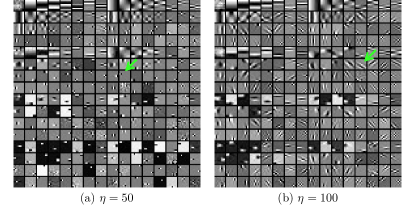

Fig. 1 shows example transforms (rows of are reshaped as patches and the first slices of such 3D patches are shown) learned from patches of an XCAT phantom [54] volume. The transform learned with in (P0) has more oriented features whereas the transform learned with shows more gradient (or finite-difference) type features (pointed by the green arrows). This behavior suggests that a single ST may not be rich enough to capture the diverse features, edges, and other properties of CT volumes. Therefore, next we consider the extension of the ST approach to a rich union of learned transforms scheme.

Recall that in Section IV.F, we used the transforms learned from the patches of the XCAT phantom volume to perform reconstruction of the chest volume from helical CT data. Alternatively, one could learn the transforms from the patches of the PWLS-EP reconstruction of the helical CT data. Fig.Β 14 shows the union of transforms () learned from patches of the XCAT phantom and the PWLS-EP chest reconstruction, with . These two union of transforms display some similar types of features, and provide similar visual reconstructions in PWLS-ULTRA (with patch-based weights ) in Fig.Β 14. Thus, the transform learning algorithm extracts quite general and effective sparsifying features for images, without requiring a very closely matched training dataset.